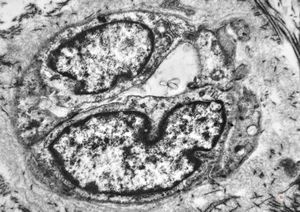

F,41y. | synovial metaplasia - capsule of implantate

F,41y. | synovial metaplasia - capsule of implantate

F,41y. | synovial metaplasia - capsule of implantate

F,41y. | synovial metaplasia - capsule of implantate

F,41y. | synovial metaplasia - capsule of implantate

F,41y. | synovial metaplasia - capsule of implantate

F,41y. | synovial metaplasia - capsule of implantate

F,41y. | synovial metaplasia - capsule of implantate

F,41y. | synovial metaplasia - capsule of implantate